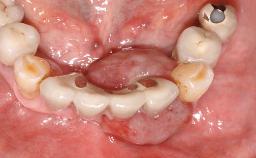

A 73-year-old woman was referred to the Division of Periodontology (University of Geneva School of Dental Medicine) after repeated unsuccessful treatment of a peri-implant infection. She was systemically healthy and did not smoke. The patient’s history revealed that, three years earlier, an immediate implant (Straumann Tapered Effect RN 4.8/4.1; Institut Straumann AG, Basel, Switzerland) had been inserted to replace the upper right central incisor. A metal-ceramic crown had been delivered using an adhesive resin cement. One year later, the patient had consulted another dentist due to discomfort in the soft tissues in the implant region. There was a suppurating peri-implant pocket, 10 mm deep. Peri-implant bone loss and excess luting cement were seen on the radiograph. The situation was treated with non-surgical debridement, amoxicillin, and repeated submucosal irrigation with a chlorhexidine digluconate solution. The patient was referred after the suppuration had persisted for several months.